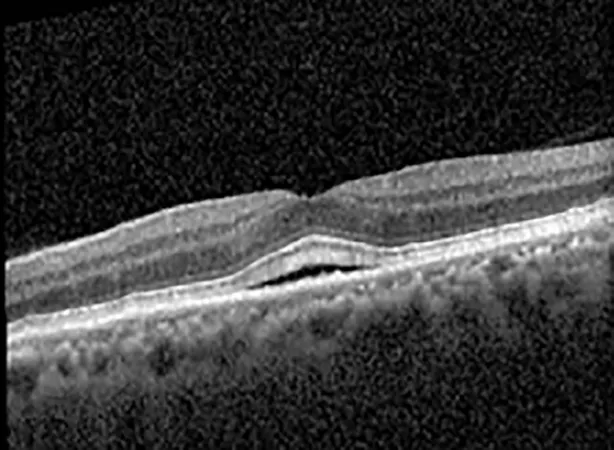

The patient began treatment with oral pemigatinib daily and was followed up for an ophthalmic examination during the second treatment cycle approximately 5 weeks into the treatment process. The patient had at this stage received 28 doses of 13.5 mg per day, which was administered in cycles of 14 on-days and 7 off-days, and had no visual or ophthalmic complaints. The non-corrected VA was OD 20/30 + 1 and OS 20/20. The OCT examinations revealed subfoveal SRF bilaterally. The fundus examination was otherwise unremarkable outside the patient’s prior documented peripheral drusen. Repeat autofluorescence was overall unchanged, though a slight hypofluorescent ring may be visualized in Figure 2. The current pemigatinib protocol recommendation for asymptomatic patients suggests no dose modification; however, with worsening presentation or positive symptoms, it is recommended to withhold pemigatinib. After discussion with the patient’s oncologist, it was decided to continue the medication at this time. Serial monitoring of the patient’s symptoms, vision, and SRF were conducted on specific days during active treatment cycles and days off-cycle to monitor the SRF. Subsequent evaluations demonstrated complete resolution of SRF while off-cycle, and asymptomatic re-accumulation of fluid while on-cycle with varying levels of VA. (Table 1) As we see demonstrated in the table below, in the later stages of the active cycles, such as day 13 of 14 of cycle 2, day 13 of 14 of cycle 3, day 13 of 14 of cycle 4, and day 14 of 14 on cycle 5, the patient’s VA showed no correlative changes based on the presence of SRF. The fluctuations in the patient’s VA certainly occurred, but were likely to be secondary to surface changes, as certain off-cycle days actually presented with lower acuities than days when the SRF was present on OCT examination.

Table 1

| Cycle, day, on/off | VA OD; OS | CMT OD; OS | OCT OD | OCT OS |

|---|---|---|---|---|

| Prior to initiation | 20/40; 20/20−2 | 274; 275 | ![]() | ![]() |

| Cycle 2, day 13/14, on | 20/30+1; 20/20 | 365; 355 | ![]() | ![]() |

| Cycle 2, day 4, off | 20/30−2; 20/20−2 | 282; 280 | ![]() | ![]() |

| Cycle 3, day 6/14, on | 20/40−1; 20/30−1 | 306; 301 | ![]() | ![]() |

| Cycle 3 day 13/14, Oon | 20/50+1; 20/30−2 | Poor tracing; 376 | ![]() | ![]() |

| Cycle 3, day 3, off | 20/30−1; 20/25 | 320; 329 | ![]() | ![]() |

| Cycle 3, day 10, off | 20/50−2; 20/30−1 | 269; 276 | ![]() | ![]() |

| Cycle 4, day 8/14, on | 20/50−2; 20/30 | 333; 317 | ![]() | ![]() |

| Cycle 4, day 13/14, on | 20/40−2; 20/25 | 360; 348 | ![]() | ![]() |

| Cycle 4, day 1, off (9/6) | 20/30; 20/25−1 | 273; 271 | ![]() | ![]() |

| Cycle 5, day 14/14, on | 20/30−1; 20/20 | 375; 364 | ![]() | ![]() |

| Cycle 5, day 6, off | 20/40+2; 20/30−2 | 276; 278 | ![]() | ![]() |

Highlights the visual acuity, central macular thickness, and the physical OCT of the macula for this patient in both the right and left eyes during various stages of the patient's chemotherapy treatment cycle.